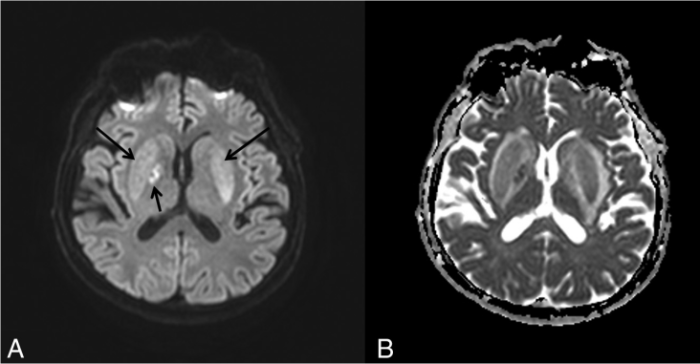

Визуализация мозга чаще всего выявляет его атрофию и увеличение желудочков. Тем не менее иногда, в ограниченном числе случаев при МРТ головного мозга можно обнаружить специфические изменения в области базальных ганглиев, хотя подобные признаки могут сопровождать и метаболический ацидоз, и метаноловую интоксикацию. Изменения, лучше всего заметные в режимах Т2-WI/FLAIR, представляют собой гиперинтенсивные четко очерченные границы скорлупы (латерально — наружная капсула, медиально — внутренняя капсула, внутренняя и наружная мозговые пластинки) с обеих сторон и в целом по форме несколько напоминающие вилку. По сути это является отображением диффузного вазогенного отека базальных ганглиев из-за нарушения процессов ауторегуляции.

- Kim D. M., Lee I. H., Song C. J. Uremic encephalopathy: MR imaging findings and clinical correlation //American Journal of Neuroradiology. – 2016.